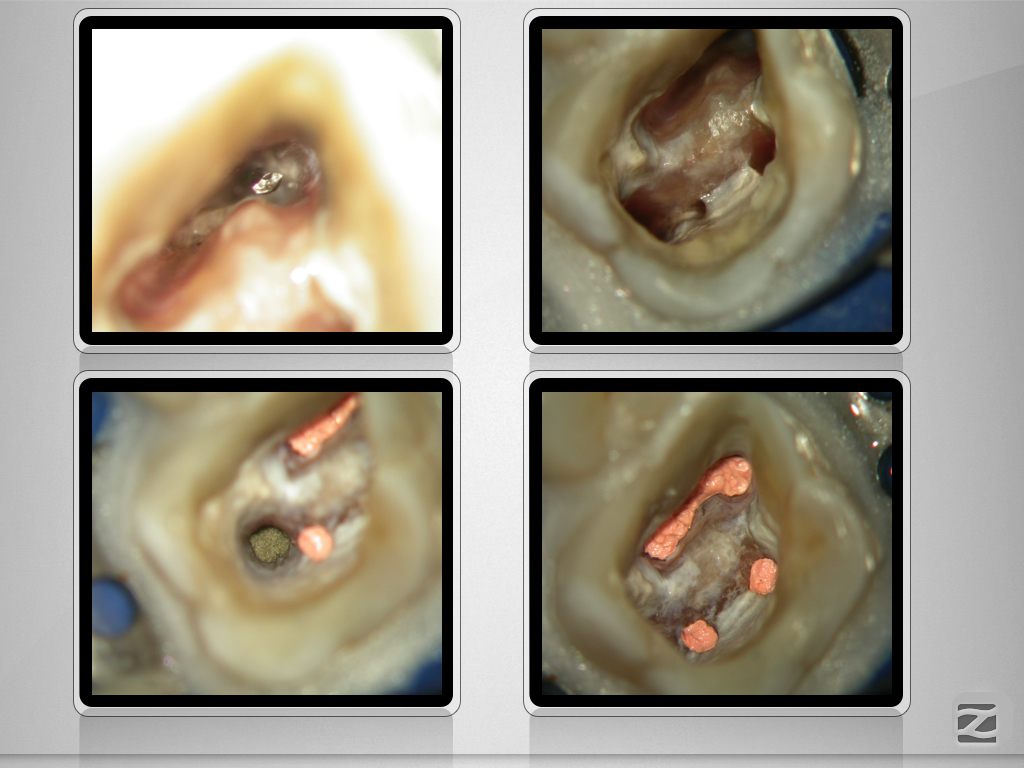

16D.010

Multiple Fragmente